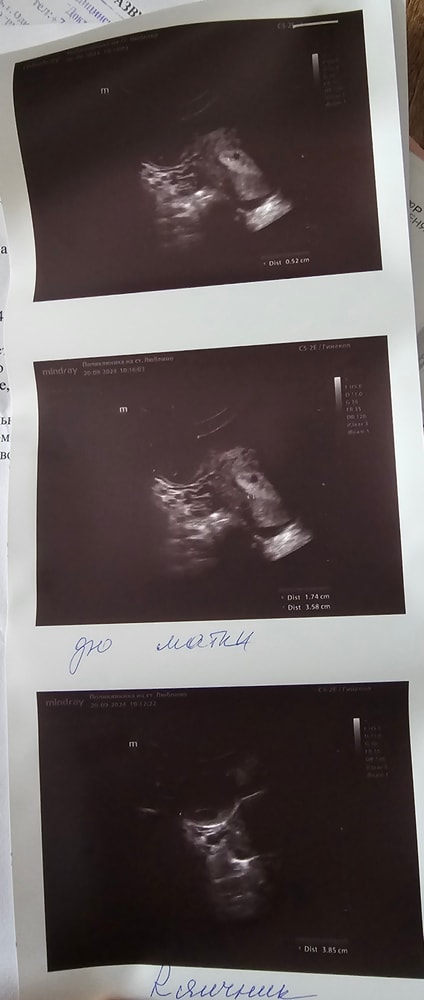

По результатам врач узист сказала, что похоже на беременность учитывая включение на дне матки 4мм (начало имплантации?), крупное желтое тело и пышный эндометрий. Но точно сказать нельзя т.к. маленький срок. Может у кого-то были похожие ситуации? Как думаете, может ли это реально быть началом беременности или 5-6 дней это слишком мало для начала имплантации?

Фото самого узи, если вдруг кто-то разбирается